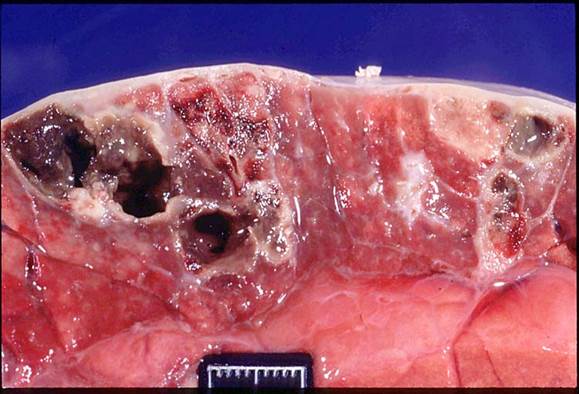

Рис. 30. Кавернозный туберкулез легких КРС

При лобарной пневмонии поражаются целые доли легкого или его обширные участки. Образуются эти участки вследствие слияния отдельных, пораженных туберкулезом долек в одном сплошном поле. Пораженные участки легкого плотные, бугристые, неравномерно окрашенные: серо-белые, желтовато-белые, разделенные прослойками соединительной ткани. При лобулярных и лобарных пневмониях происходит усиленная миграция лейкоцитов из сохранившихся сосудов. Лейкоциты своими ферментами разрушают (разжижают) казеозную массу и превращают ее в гноевидное полужидкое вещество, которое частично рассасывается, а его большая часть удаляется при кашле. После удаления казеозных масс образуются полости, называемые кавернами. В целом, при туберкулезе легких нередко обнаруживают различные по величине туберкулы и очаги пневмонии. Это объясняется неодновременным возникновением этих поражений и разной быстротой их развития, туберкулезный процесс протекает волнообразно: периоды альтерации сменяются периодами пролиферации и заживления.